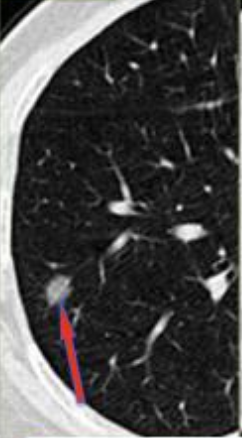

网上/APP上预约诊疗、现场自助机取号、自助缴费,整个过程非常顺畅,一气呵成,终于轮到我的主人看病了,来一个现场的照片。影像科专家说需要做一个小结节分析,于是又给了我一个特写。

原来这是目前最先进的AI分析软件,可以精确的看到我体内小结节的密度、位置及与血管的关系,听说他们还有国际上最先进的64排PET-CT,可以提供小结节的代谢信息,协助诊断小结节的良恶性和全身整体情况。我的主人很焦虑,非要做PET-CT,但程颖教授和蔼地说:“目前您肺部的结节直径只有7mm,是一个亚实性结节,PET-CT检查暂时没有必要,您可以先戒烟,3个月后复查,到时候根据检查结果再探讨下一步治疗方案……”